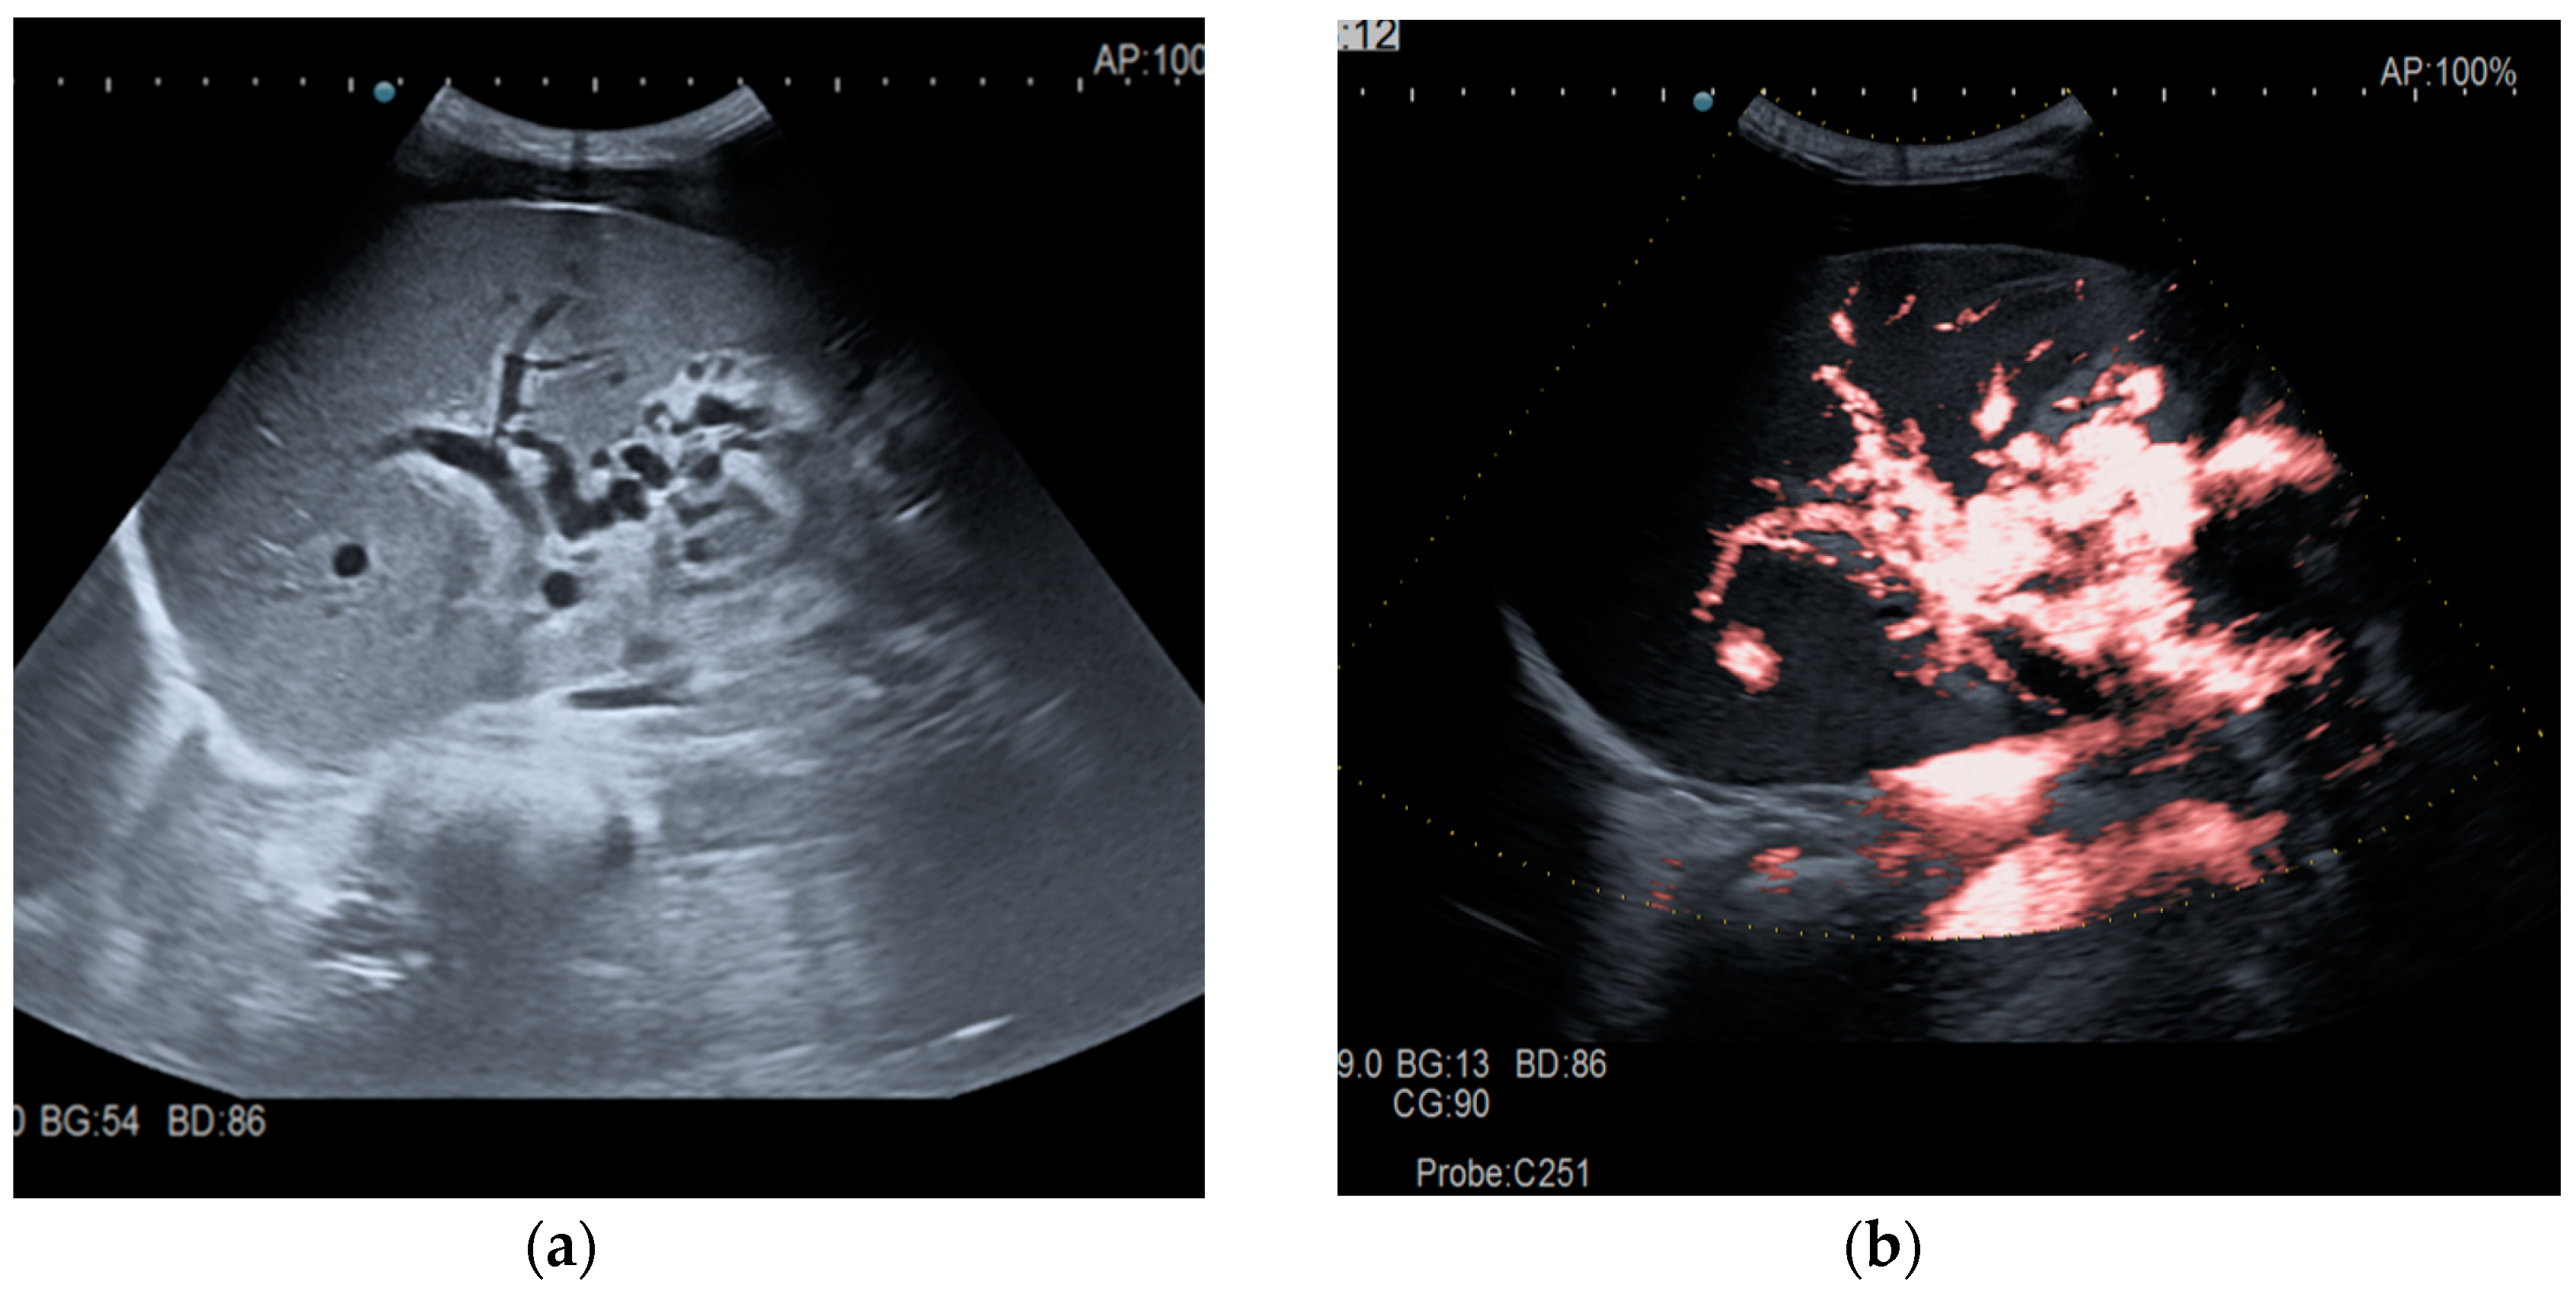

The diagnosis of PVT and PC is made by imaging procedures (transabdominal ultrasound with a Doppler or contrast-enhancing computed tomography scan, magnetic resonance imaging, or angiography in the case of therapeutic intended procedures) [1,3,12,13,14,21,29]. Transabdominal ultrasound is a reliable procedure in 60–100% of cases, with an anechoic aspect in recent cases (requiring Doppler examination or CEUS) and a hypoechoic or hyperechoic aspect in chronic cases [22,29]. Doppler examination may show an anechoic or hypoechoic thrombus and a slower (<15 cm/sec) or absent portal blood flow, and is considered the gold standard (color Doppler) for the diagnosis of PC [1], with a sensitivity and specificity of 95% (Figure 1 and Figure 2) [22]. CEUS can help the diagnosis of benign or malignant PVT, can characterize associated focal liver lesions [30], allows a better characterization of PVT [31], and also permits better detection of PC—Figure 3 and Figure 4 [32]. CT scan and MRI (Figure 5 and Figure 6) are more accurate for the evaluation of liver causes (HCC, abscesses, and other tumors) or other local causes (pancreatitis, diverticulitis, and appendicitis), and for complications (bowel infarction or perforation), and may show permeability of the portal venous system and the flow direction [1,22]. Malignant PVT has intra-thrombus arterial signals on CT, MRI, and/or CEUS, with portal vein diameter frequently 23 mm or above, and with the presence of the tumor at imaging examination (Figure 4 and Figure 6) [21].

Figure 2.

Portal cavernomatous transformation. (a) Portal vein cannot be identified; instead, meandering venous branches are visible in the porta hepatis, indicating portal vein thrombosis and consequent cavernous transformation. (b) Power Doppler ultrasonography identifies flow within the vessels.

Transabdominal ultrasound with Doppler protocol (Figure 1a,b and Figure 2a,b), CT scan (Figure 3a,b), and MRI (Figure 4a,b) were used for the diagnosis in 88.9, 75.1, and 15% of cases, respectively. CEUS was used for the diagnosis in 49 cases (25.9%) but in only 29 cases was it used for the evaluation of the thrombus, and in two cases for cavernoma diagnosis (Figure 5a,b and Figure 6a,b).